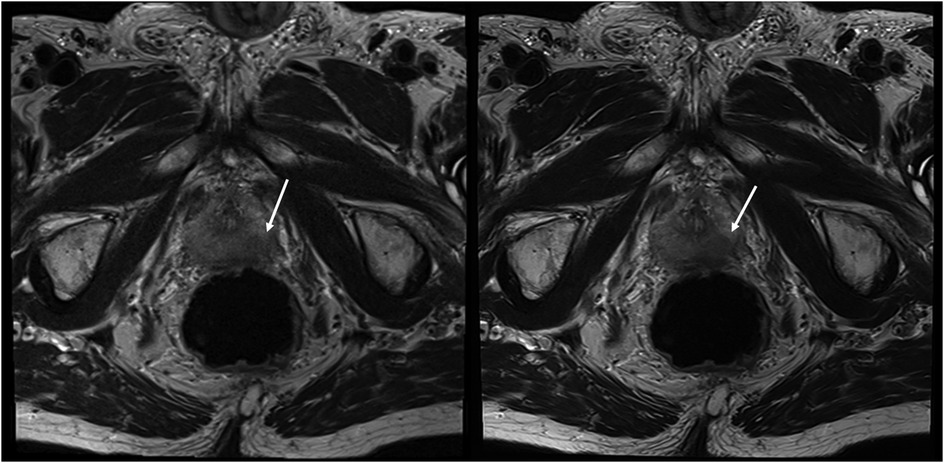

The sharpness of the prostate was evaluated to be significantly superior in T2HR compared to T2S, with medians of 5 (4–5) vs. 4 (4–4) (p < 0.001). The contours of the lesion were also rated superior, with a median of 5 (4 -5) in T2HR vs. a median of 4 (4–4) (p < 0.001). The delineation of the prostate border was also rated to be improved in T2HR [median of 5 (4–5)] as compared to T2S [median of 4 (4–5); p < 0.001]. However, the extent of the motion artifacts was evaluated to be worse in T2HR compared to T2S, with medians of 5 (4–5) vs. 5 (5–5) (p = 0.009). Please see Table 3 for the full details. Figures 2–4 show examples of both sequences.

Figure 3. Imaging of a 78-year-old man with suspicion of prostate cancer. T2S on the left-hand side and deep learning-reconstructed T2HR on the right-hand side. T2HR demonstrated improved delineation of the suspicious area (arrow). Both readers rated this case in both sequences as PI-RADS 5 with extraprostatic extension. The lesion size was 23 mm and the length of the capsule contact was approximately 16 mm.